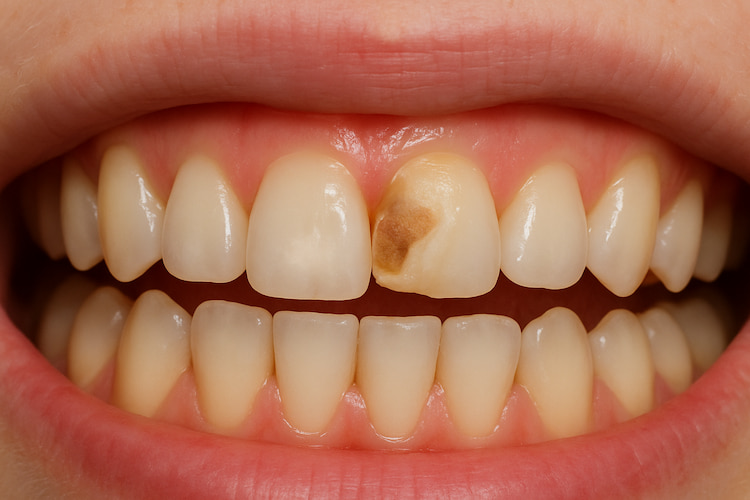

A cavity progresses through several distinct phases, each characterized by its own unique visual signs. When dental cavities first start, they may look like white spots. Over time, these spots become brown or black areas that eventually transform into holes in the tooth, requiring dental treatments, such as a dental filling. Diagnosis of these changes early can help to avoid further damage and enable early dental intervention.

As the damage to tooth enamel extends, it breaks through just below the teeth, becoming a light brown and chalky design. It can also feel rougher than the rest of your enamel. A certified medical expert must remove the decay and make fillings in your tooth.

Visual Inspection of Cavities

You can sometimes spot early signs of tooth decay just by looking in the mirror. At first, cavities may appear as chalky white spots, a sign that the enamel is beginning to lose minerals. As decay progresses, these spots can turn light brown or dark brown and may form visible holes or pits on the surface of your teeth. If you notice any discoloration, rough spots, or visible damage, it’s best to book a dental appointment right away.